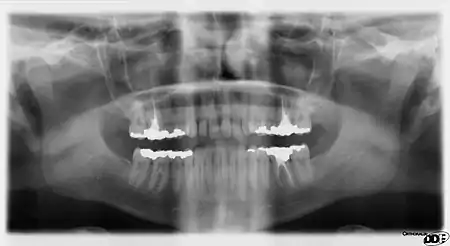

It is possible for both tooth decay and periodontal disease to be missed during a clinical exam, and radiographic evaluation of the dental and periodontal tissues is a critical segment of the comprehensive oral examination. The photographic montage at right depicts a situation in which extensive decay had been overlooked by a number of dentists prior to radiographic evaluation.

Panoramic films are extraoral films, in which the film is exposed while outside the patient's mouth, and they were developed by the United States Army as a quick way to get an overall view of a soldier's oral health. Exposing eighteen films per soldier was very time consuming, and it was felt that a single panoramic film could speed up the process of examining and assessing the dental health of the soldiers; as soldiers with toothache were incapacitated from duty. It was later discovered that while panoramic films can prove very useful in detecting and localizing mandibular fractures and other pathologic entities of the mandible, they were not very good at assessing periodontal bone loss or tooth decay.[18]